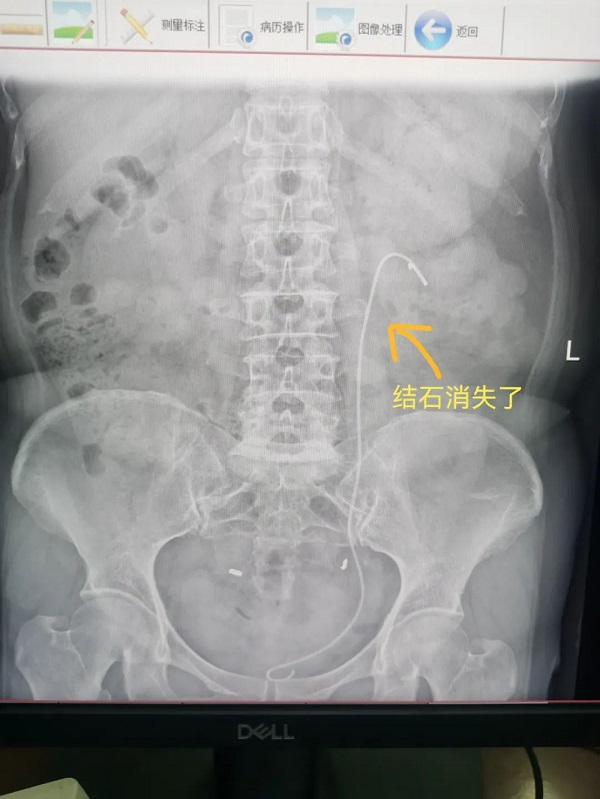

65岁杨大姐和50岁的潘大姐就是这种手术的受益者,她俩均因为腰痛来我院泌尿外科门诊咨询就诊,医生诊断为肾结石,并建议她们做输尿管软镜手术治疗,通过医生的详细介绍,杨大姐和潘大姐对这种没有任何刀口的手术方式表示很惊讶,紧张的心情一下子就放松了。

通过应用负压吸引鞘,主任医师辛明辉、副主任医师刘伟带领泌尿外科团队在麻醉医师的通力合作下,对结石进行了完全清除,手术均顺利完成。经过术后康复,杨大姐和潘大姐在手术后第三天就顺利出院了。

2.将粉碎结石快速吸出体外,缩短手术时间,提高清石率,清石率可达90%以上,避免反复手术;